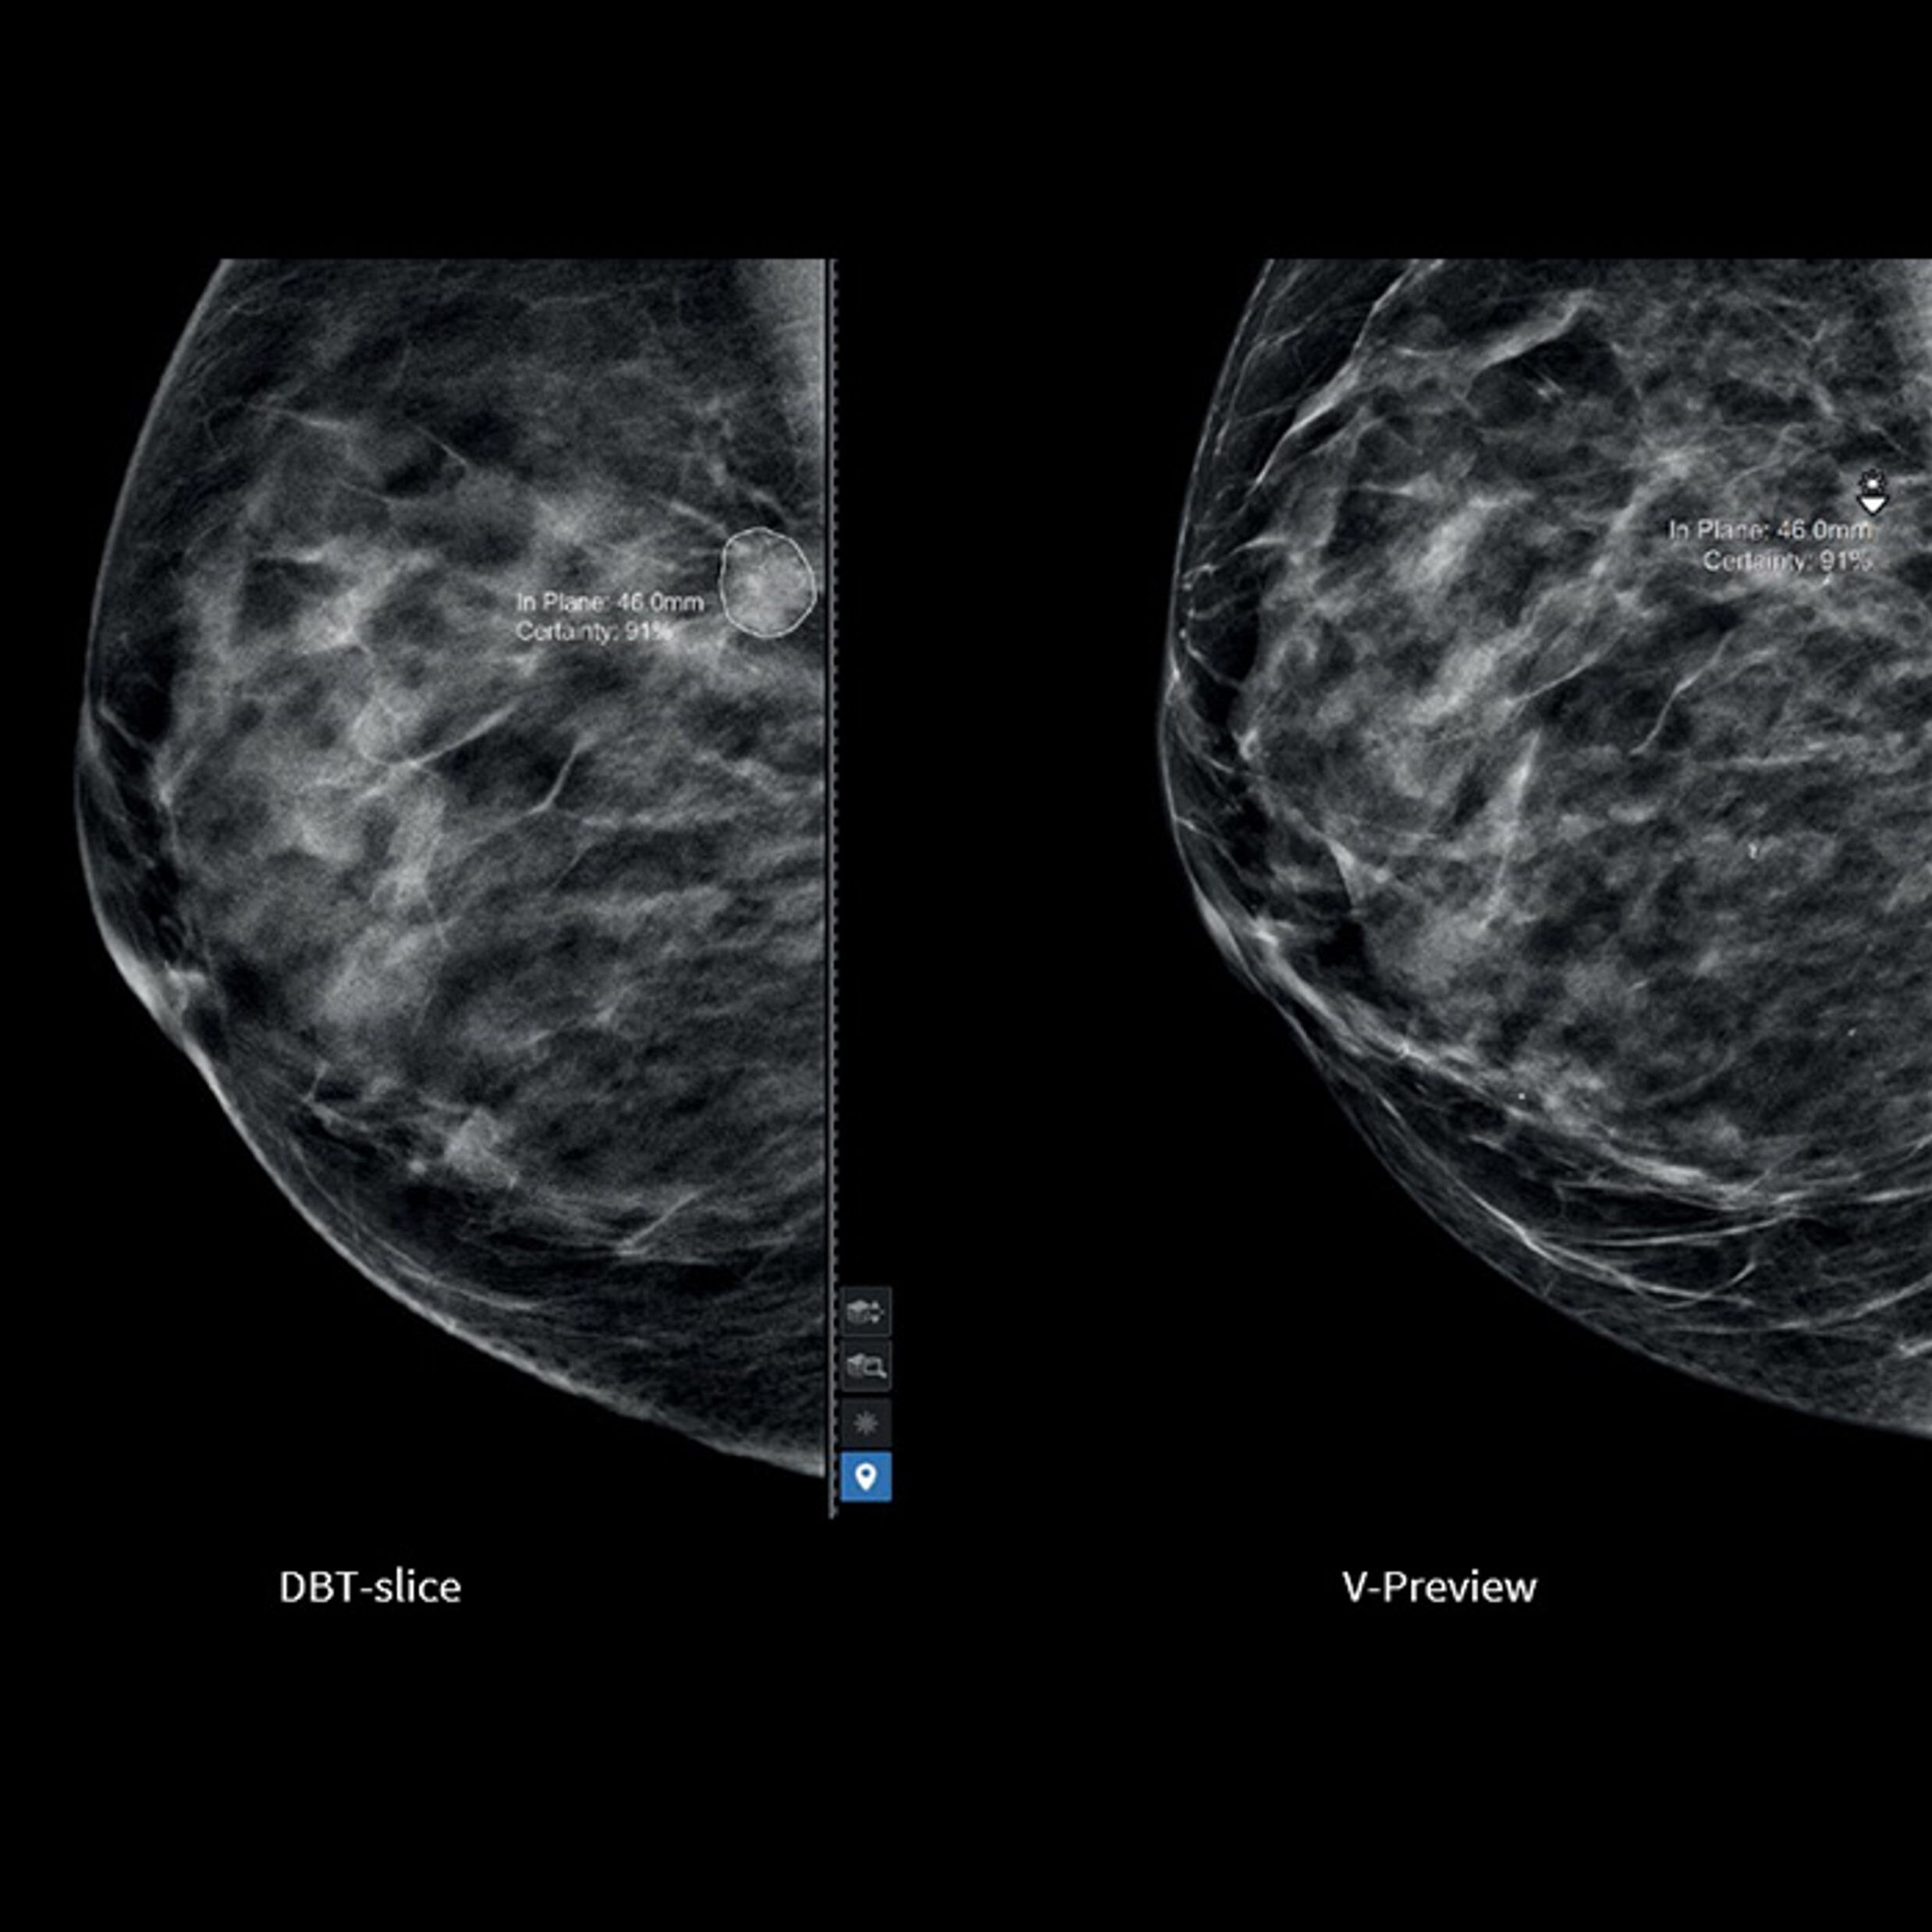

TrueFidelity DL + True Enhance DL

Better together

With the Revolution Ascend Platform, you can combine both of our AI-based imaging reconstruction technologies to create one stunning image. By combining True Enhance DL with TrueFidelity DL, you can achieve images that have less noise, enhanced sharpness and better noise texture than images obtained with ASiR-V.

True Enhance DL

Designed to enhance what matters

True Enhance DL is a deep learning-based processing method intended for contrast enhancement of single energy images. True Enhance DL uses a dedicated Deep Neural Network (DNN) trained to estimate monochromatic, 50 keV GSI images from single-energy X-ray. This technology brings four deep learning models that the user can choose depending on different contrast enhancement phases by clinical tasks.